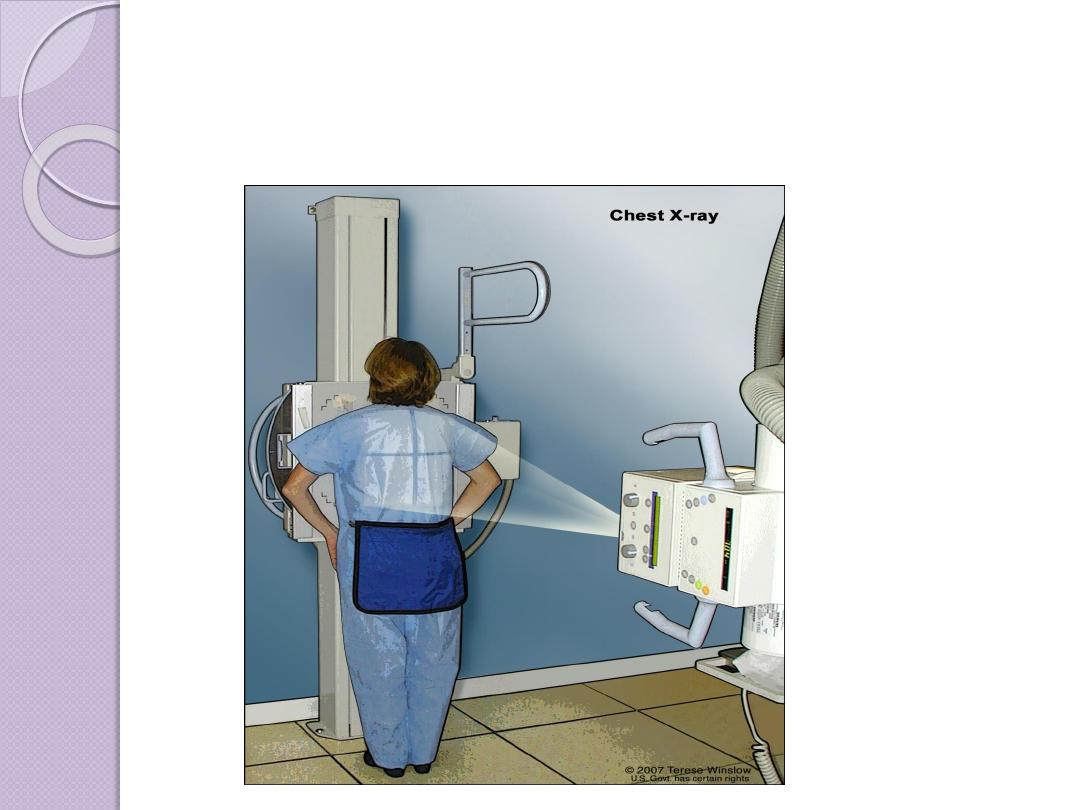

Radiographic Views

Chest and abdominal films are referred to as upright or

supine, depending on the position of the patient. In

addition, chest x-rays are usually described as

posteroanterior (PA) or anteroposterior (AP) or

lateral

These terms indicate the direction in which the x-ray

beam traversed the patient on its way to the detector.

PA means that the x-ray beam entered the posterior

aspect of the patient and exited anteriorly. AP means

that the beam direction through the patient was

anterior to posterior. A left lateral decubitus view is

one taken with the patient’s left side down.